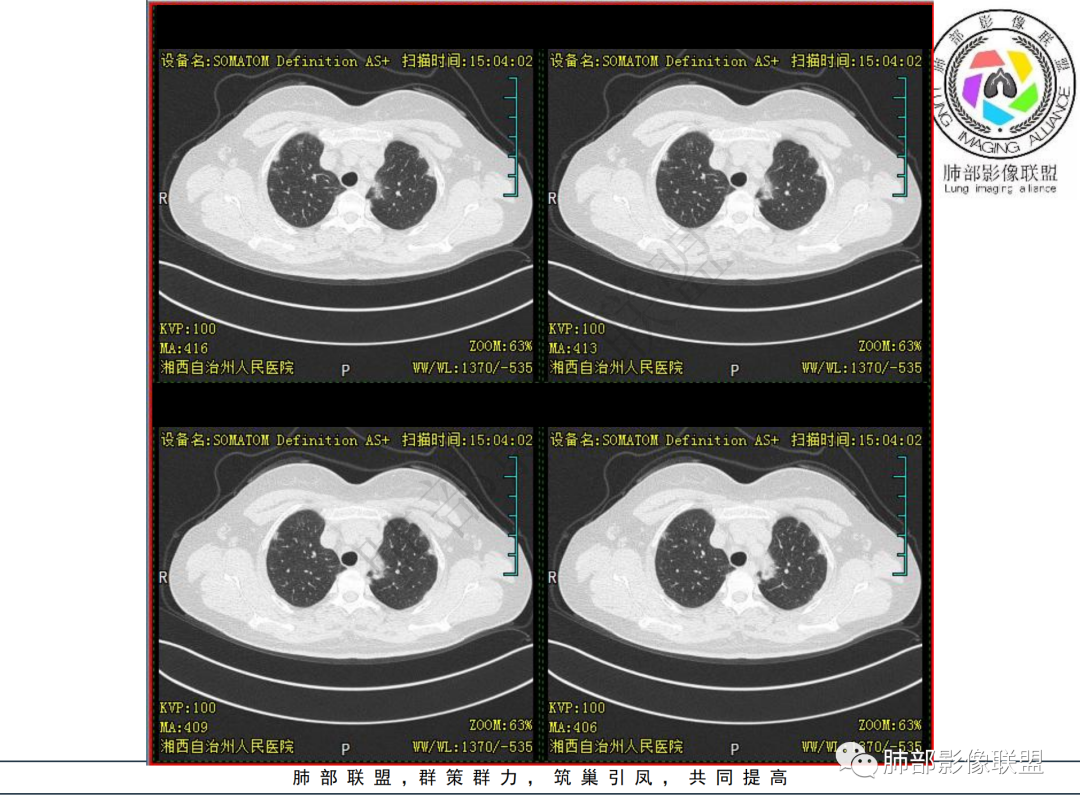

中年妇女,类风湿性关节炎病史,RF升高,感染性指标正常,双肺散在多发结节、斑片、条片灶,边缘欠清晰,大部分胸膜下分布,部分反晕,考虑RA-ⅠLD ,OP样改变

中年女性,有类风湿关节炎病史,双肺内及胸膜下见多发结节,条索状及小实变影,部分结节病灶垂直支气管血管束生长,部分结节病灶内见偏心性空洞形成,病灶收缩力弱,病灶形态多样,部分可见纤维化样改变,整体符合Op表现,结合患者病史,考虑类风湿结节,隐球菌感染不能排除。

中年女性,类风湿关节炎病史,双肺散在结节影,胸膜下分布为主,部分可见小空洞影,部分可见索条影,OP样改变,考虑类风湿结节,鉴别隐球菌

双肺散在多发结节及斑片,边缘欠清晰,胸膜下分布为主,部分内可见支气管扩张,妇女,类风湿性关节炎病史,RF升高,感染性指标正常,考虑RA-ILD,鉴别淋巴瘤。

双肺多发斑片影、结节影,胸膜下分布为主,部分沿支气管血管束分布,病灶大部分边缘平直。

双肺多发结节状及斑片状不均质磨玻璃病灶,胸膜下分布为主,边缘有收缩、凹陷,部分反晕,病灶内可见支气管扩张。中年女性,类风湿关节炎,感染指标正常。类风湿结节?隐球菌?

女,49岁,类风湿因子升高,影像双肺斑片及小结节影,胸膜下分布为主,部分病灶内支气管扩张,双侧胸膜增厚,复查病灶增多增大,考虑RA_ILD。

女性,49岁,多关节肿痛1年余。RF升高。胸部CT:双肺多发斑片影、结节影,胸膜下为主,部分沿支气管血管束分布,大小不等,部分病灶内支气管扩张,部分呈反晕,部分呈楔形宽基底贴附胸膜,复查CT进展,考虑:CTD—ILD?OP?鉴别血管炎、HP、肺梗、曲霉等。

中年女性,多关节肿痛一年,类风湿因子增高,双肺及胸膜下可见多发大小不一结节,部分呈楔形,以胸膜下分布为主,边缘平直,部分病灶分布于支气管血管束,部分可见空气支气管征、反晕征,复查病灶进展,类风湿结节?OP?

胸部CT提示双肺多发的斑片实变结节影,磨玻璃。病灶分布以双肺胸膜下为主,部分病灶以支气管血管素分布,病灶内可见支气管穿行。总体符合间质性肺疾病。

2.双肺多发片状影,胸膜下分布为主,部分沿支气管血管束分布,边界不清,实性及磨玻璃密度,趋于柔和,可见支气管进入或穿行,未见空洞、钙化及树芽等。部分病灶显示反晕。